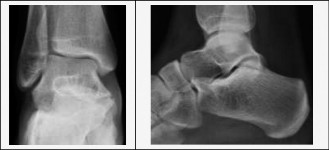

Thorough preoperative planning relies heavily on advanced imaging. While weight-bearing orthogonal radiographs of the foot and ankle are the starting point, they are often insufficient for complete surgical planning. Radiographic signs such as the "C-sign" (continuity of the talar dome and sustentaculum tali) and the "anteater nose sign" (elongation of the anterior process of the calcaneus) suggest TC and CN coalitions, respectively.